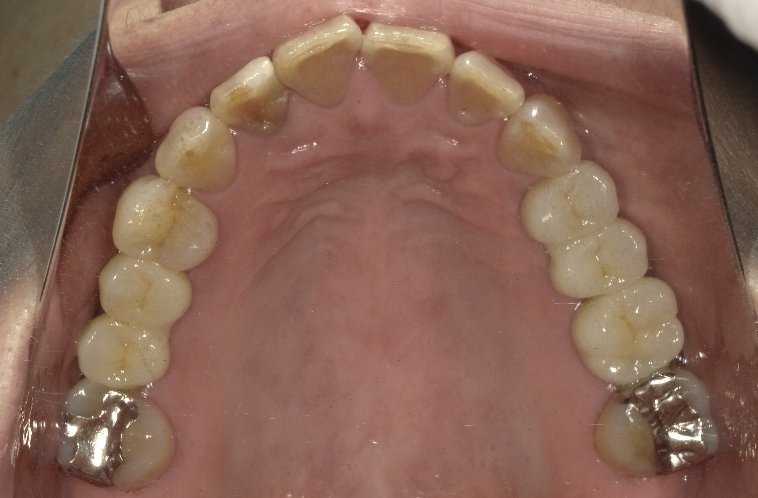

虫歯治療decay

インプラントimplant

歯周病perio

咬合治療occlusion

審美歯科esthetic